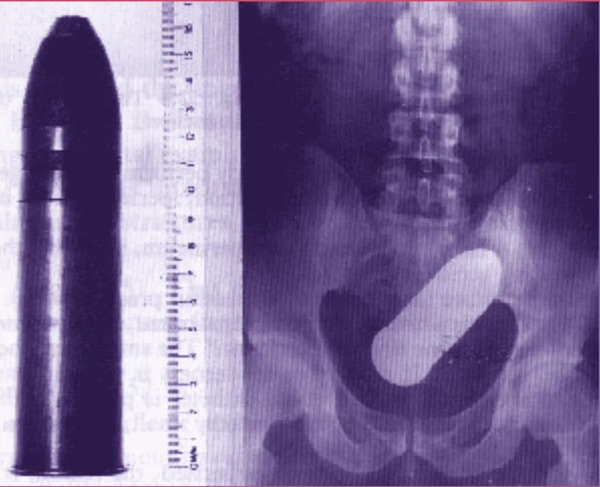

La scène a de quoi prêter à sourire, ou à grimacer : un jeune homme de 24 ans se présentant aux urgences de Toulouse avec un obus de 16 cm datant de 1918 dans le rectum. L’hôpital partiellement évacué, les démineurs dépêchés, les pompiers, la police… Un déploiement de forces publiques et de moyens considérables pour un acte d’une débilité certaine. Mais au-delà du fait divers sordide, cette histoire est une parfaite allégorie de la France contemporaine : l’irresponsabilité individuelle génère un